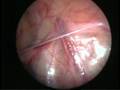

Can this operation done by laparoscopy?

Operation in hernia involves closing of the open passage through which the testis has come down. This can be done from outside as in open surgery or from inside by laparoscopy. If your child has got a hernia on one side, there is a 15 – 25 % chance that he / she may develop a hernia on the opposite side at a later date. With the help of laparoscopy we are able to look at the opposite side to see if the passage is open on that side as well. This can be closed at the same sitting if you wish to. Recovery from surgery, timing of surgery and discharge from hospital are the similar for open surgery and laparoscopic surgery.

Laparoscopic repairs have a slightly higher chance of recurrence (i.e. the hernia coming back again) as compared to open hernias. You can discuss the pros and cons in details with your doctor when you come for consultation.